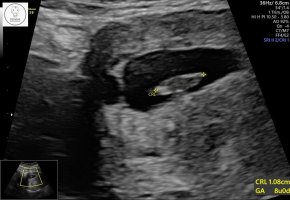

Så rart, vi har termin samme dag og jeg er 7+1. Min var 11 millimeter. Kanskje din er større? (Synes dette var interessant) Gratulerer så masse uansett <3Alt perfekt![]()

Målte tilsvarende 7+5, som er en dag lenger enn vi var (7+4)

12,7 millimeter her, og dette er IVF-baby, så vi vet på timen hvor gammel den erSå rart, vi har termin samme dag og jeg er 7+1. Min var 11 millimeter. Kanskje din er større? (Synes dette var interessant) Gratulerer så masse uansett <3

Så spennende! Fikk litt wow følelse av hvor presist det kan være. Veldig gøy også!12,7 millimeter her, og dette er IVF-baby, så vi vet på timen hvor gammel den er![]()